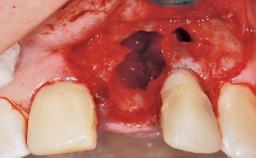

Late Flapless Placement of an Implant in a Maxillary Left Central Incisor Site

A 39-year-old male patient presented with a chief complaint of discomfort and gingival discoloration around his maxillary left central incisor. He was in good general health and was a non-smoker. His past dental history was significant because of the traumatic fracture of tooth 21 in a sporting accident at age 13. Initial dental treatment included endodontic therapy and a full-coverage restoration. The patient became symptomatic 5 years later, when structural failure of the tooth resulted in the dislodgment of the crown. Endodontic retreatment, apical surgery, and post-and-core restoration were performed.

Soft Tissue Anatomy Intact Defective

Bone Volume Horizontally and vertically sufficient Horizontally deficient Deficient vertically or deficient vertically AND horizontally